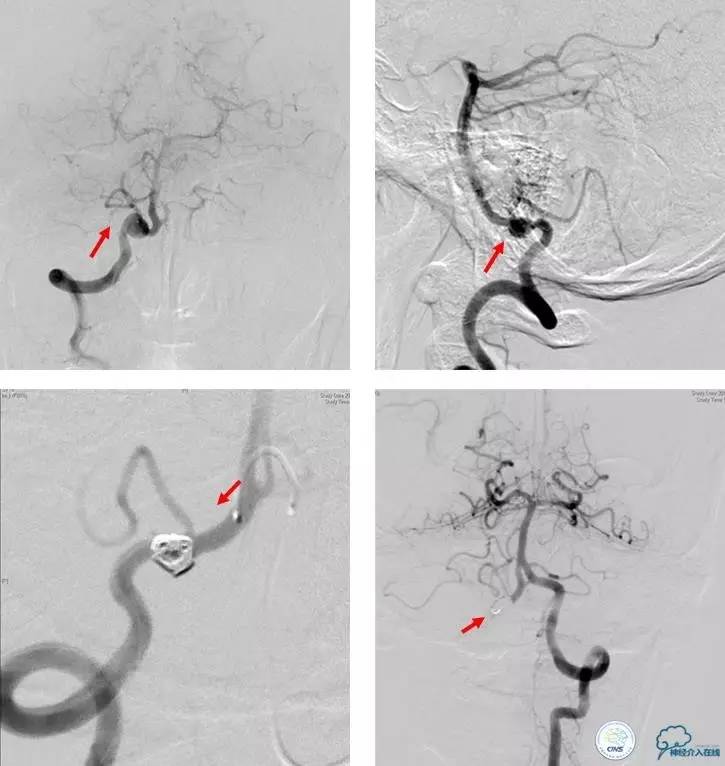

血管造影影像,提示右侧椎动脉V4段夹层动脉瘤伴重度狭窄

医生给小陈做了全脑血管造影证实了椎动脉夹层,并实行了逆行弹簧圈栓塞术+椎动脉闭塞术。

术中脑血管造影